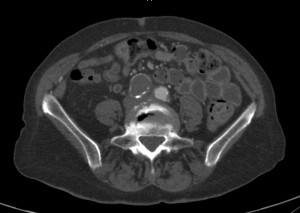

An iliac artery aneurysm is a dilatation of the iliac artery. A normal iliac artery measures up to 1 cm in diameter. An iliac artery that is wider than that is aneurysmal.

Isolated iliac artery aneurysms are uncommon. For reference, aortic aneurysms are perhaps present in 4% of people. An aneurysm in the iliac artery exists in 0.1%. These aneurysms are more common in conjunction with an aortic aneurysm. In any case, symptoms are rare. That is why diagnosis is usually incidental. Abdominal or even lumbar imaging may show this finding. The aneurysms are categorized by location: internal, external or common iliac artery. Common and external iliac artery aneurysms are actually more common than in the internal iliac artery.

Decisions of whether to treat depend on several factors. First, whether the iliac aneurysm is isolated or not. If the iliac aneurysm accompanies an aortic aneurysm a joint decision may be a way to go. This is particularly true if the aortic aneurysm is treated with a stent-graft. Then the limbs of the graft are deployed in the iliac artery and by that the aneurysm is excluded.

Isolated aneurysms can be followed, treated with endovascular techniques or operated upon. Surgical repair is considered major vascular surgery and is risky. The literature about aneurysm size and rupture rate is disappointing, especially regarding internal iliac artery aneurysms. Once review examining all case reports to 2014 noted that aneurysms in the internal iliac artery that were asymptomatic measured 5.1 cm and those that did rupture were larger (6-7 cm).

Indications for intervention depend on aneurysm size, growth rate and symptoms. Consider intervention once an aneurysms reaches 3-4 cm should be treated. An aneurysm greater than 5 cm should be treated expeditiously. Interestingly, in a retrospective report of 236 femoral artery aneurysms there were no complications in aneurysms that measured less than 3.5 cm. While this is obviously a different artery, this data supports the above size thresholds.